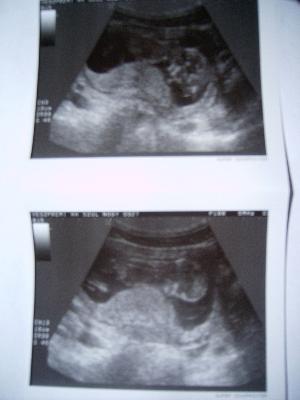

A diagnózishoz ultrahang vizsgálaton is jellegzetes képet kapunk, a pontos diagnózis a megfelelő hormonvizsgálatok elvégzése után lehetséges korrekt módon. Ilyen kivizsgálás olyan klinikán, vagy kórházban lehetséges, ahol van ultrahang és hormonlabor.